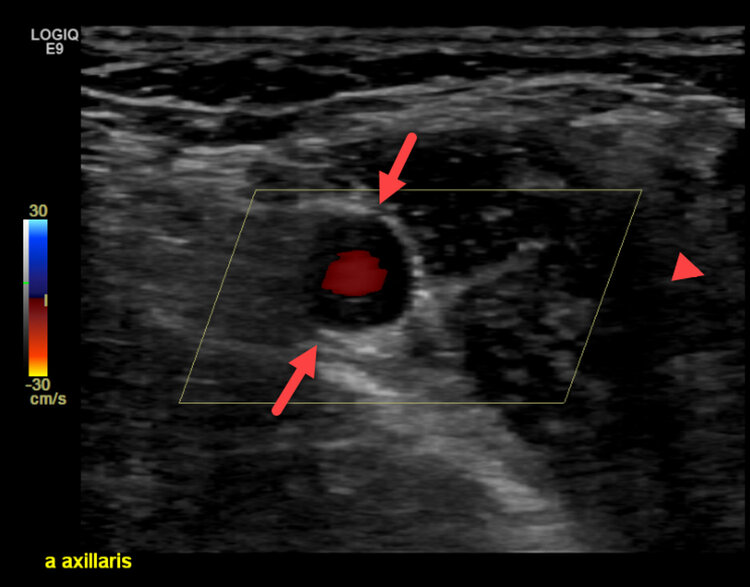

Die Vaskulitis ist eine Entzündung der Blutgefässe, die zu Schäden an der Gefässwand führt, meist eine Wandverdickung (Abbildung 1a/b). Die Ursachen für eine Vaskulitis sind noch nicht vollständig geklärt, aber es wird angenommen, dass eine überaktive Immunreaktion eine Rolle spielt.

Eine Früherkennung und Vorbeugung der Vaskulitis ist schwierig. Eine prompte Diagnose ist jedoch wichtig, um Schäden an den betroffenen Gefässen zu vermeiden. Die Diagnose erfolgt über Klinik, Laborwerte, Duplexsonographie (Abbildung 1a/b). Die Beurteilung mittels Kapillarmikroskopie kann Hinweise auf eine Bindegewebserkrankung geben (Abbildung 2a/b).